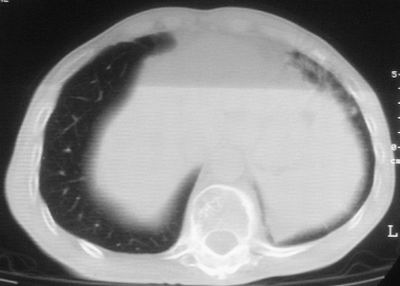

标题: CT11864:男,47岁,反复咳嗽、咯痰、咯血3年,请分析. [打印本页]

患者,男,47岁,反复咳嗽、咯痰、咯血3年,再发5天。痰培养未找到真菌、抗酸杆菌、癌细胞。

左肺上叶体积明显缩小,其内见多发透光区,纵隔向左侧移位,左肺下叶多发班片状病灶,边界模糊,1左肺上叶先天肺发育不全,2左肺下叶肺炎,

左肺上叶结核伴肺纤维化,纵隔移位,左肺下叶感染性病变,建议抗炎抗结核后复查,双肺气肿.

考虑:左肺慢纤伴霉菌球形成、双肺全小叶型肺气肿。

1)考虑为:左肺上叶肺结核(空洞形成),伴左下肺感染;不排除霉菌感染可能。2)肺气肿。

左肺上叶结核伴肺纤维化空洞形成并左肺下叶感染,纵隔牵拉移位,建议作进一步检查排除左侧肺霉菌感染可能。